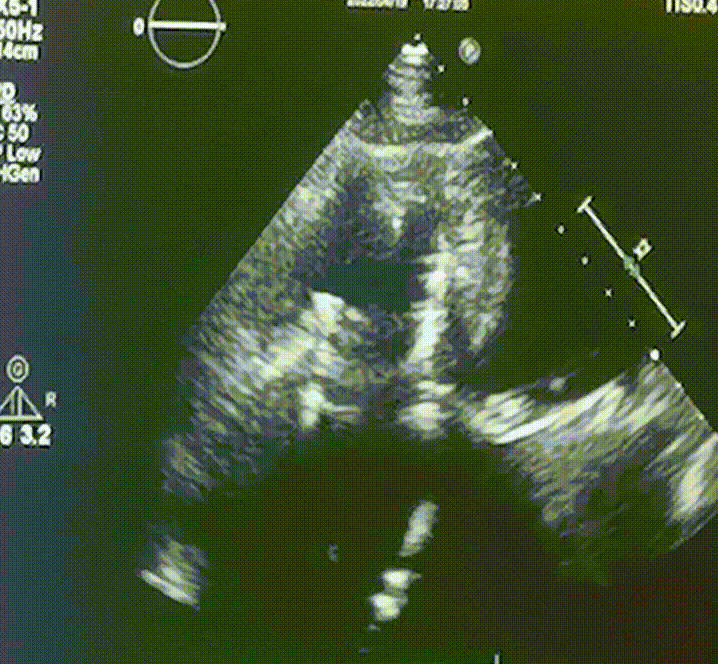

此次手術在全麻下進行,采用經右側頸靜脈入路。術中在經食道超聲和DSA的指引下多個維度精細調整輸送器角度,在達到正確位置后,逐步釋放瓣膜錨定裝置和盤片,最終完成瓣膜植入。術后患者右房壓明顯下降,術后超聲提示人工三尖瓣同軸性良好,瓣架固定牢靠,無反流和瓣周漏,血壓術后即刻上升20mmHg左右,手術后監護室順利拔除氣管插管,3天后恢復良好,予以出院。

圖2.術后超聲